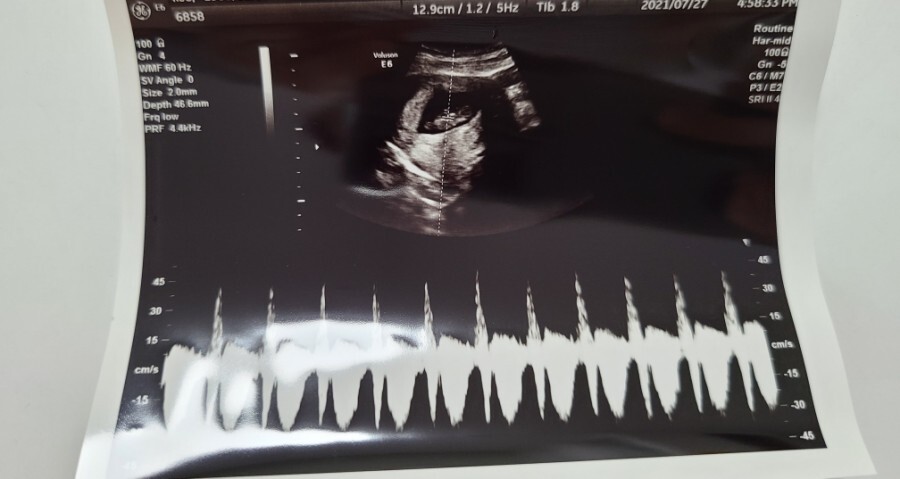

10주 차부터는 보통 질 초음파가 아닌 복부 초음파로 아기의 상태를 확인할 수 있다고 하셔서 복부 초음파로 아기의 상태를 확인했어요.

복부 초음파로 확인한 우리 아기의 크기는 3.45cm로 주수에 맞게 잘 크고 있다고 하시더라고요.

심장 소리도 지난번보다 더 우렁차졌다고 하셔서 조금은 안심할 수 있었고 이젠 제법 사람의 형태가 보이는 것 같아 신기하기도 했어요.